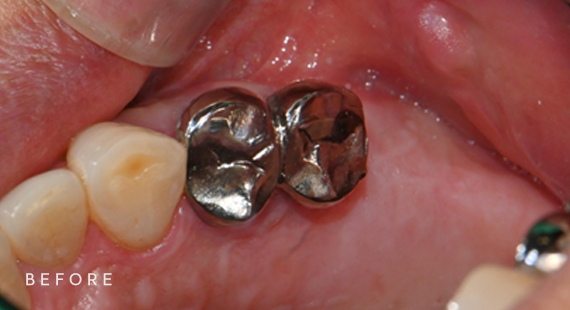

충치치료